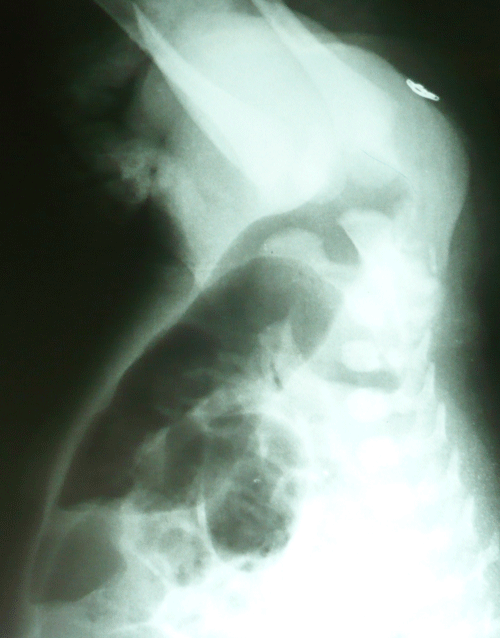

A 36-hour-old male neonate presented with imperforate anus and abdominal distension. There was no meconuria. Antenatal fetal anomaly scanning had not been done. Except for mild tachypnea (respiratory rate 60/min) physical examination of chest was nothing abnormal. Ultrasound of the abdomen did not reveal any anomaly. Invertogram (Fig. 1) showed a high variety imperforate anus. A sigmoid colostomy was performed. The colostomy started moving and patient was allowed orally the following day. The patient developed respiratory distress after starting feeds. A chest radiograph showed eventration of left hemidiaphragm (Fig. 2). A nasogastric tube inserted for gastric decompression alleviated the respiratory distress. The patient underwent plication of the diaphragm electively on 8th day of life. Postoperative recovery was uneventful. The patient is lost to follow-up.

Figure 1: High variety Imperforate anus. |